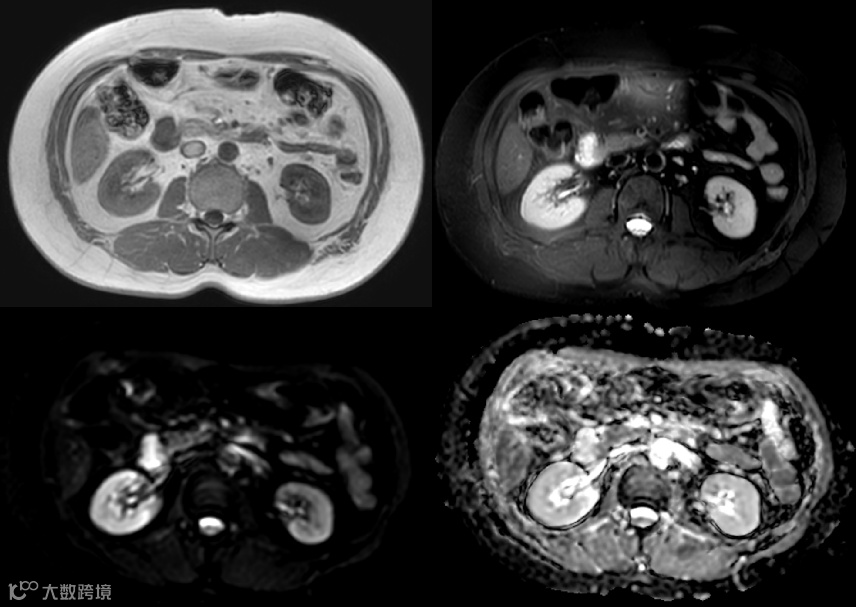

女性,77岁

主诉:上腹烧灼感1周余

现病史:患者近1周余偶有上腹烧灼感,偶有反酸,大便 2-3 次/日,成形色黄

胃镜检查:1.球降交界处粘膜隆起(性质待查) 2.胃体隆起(外压?) 3. 慢性胃炎急性活动

既往史:2019年于我院因结节性甲状腺肿行手术治疗,术后口服优甲乐,恢复可;2020-03-17在全麻下行右侧保留乳房的乳腺癌切除术,术后病理:浸润性癌病理分期:ⅡA(T2,sN0,M0)

影像学表现